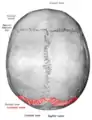

Lambdoid suture

Lambdoid suture (shown in red line)

The lambdoid suture (or lambdoidal suture) is a dense, fibrous connective tissue joint on the posterior aspect of the skull that connects the parietal bones with the occipital bone. It is continuous with the occipitomastoid suture.

The lambdoid suture is between the paired parietal bones and the occipital bone of the skull. It runs from the asterion on each side.

The lambdoid suture is named due to its uppercase lambda-like shape.